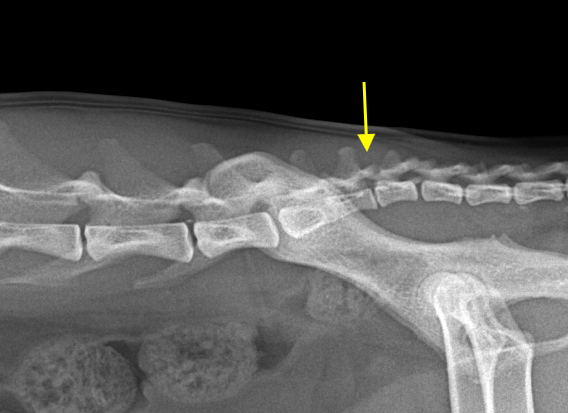

고양이 요천추간 이상 병변은 흔하게 관찰되는 병변이다.

즉, 요천추의 이상이 선천적이든 후천적이든, canal stenosis와 변비 발생 가능성을 높인다는 것. 무시할 수 없는 영역의 문제로 방사선 검사에서 관찰된다면 해당 고양이는 반복적으로 이상 여부를 평가하기 위한 건강검진을 정기적으로 받아 야한다는 말이다.